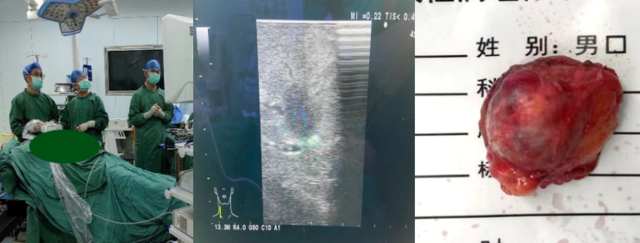

泌尿外科张曦医生介绍,手术过程简洁但不简单:病人采取全身麻醉,麻醉成功后摆术中侧卧位,于患侧腰部取三个长约1.5cm的微创切口,进入微创手术器械,小心分离,显露出患侧肾脏,因此类患者肿瘤较小,术中为确认肿瘤位置及边界,还需借助一利器,即术中B超,大大帮助医生进一步确认肿瘤位置大小,降低手术风险,将肿瘤完整切除。手术后患者将在专业团队的帮助下进行术后恢复。

▲张曦主任为患者手术

▲术中B超显示肾肿瘤

▲术后切除的肿瘤